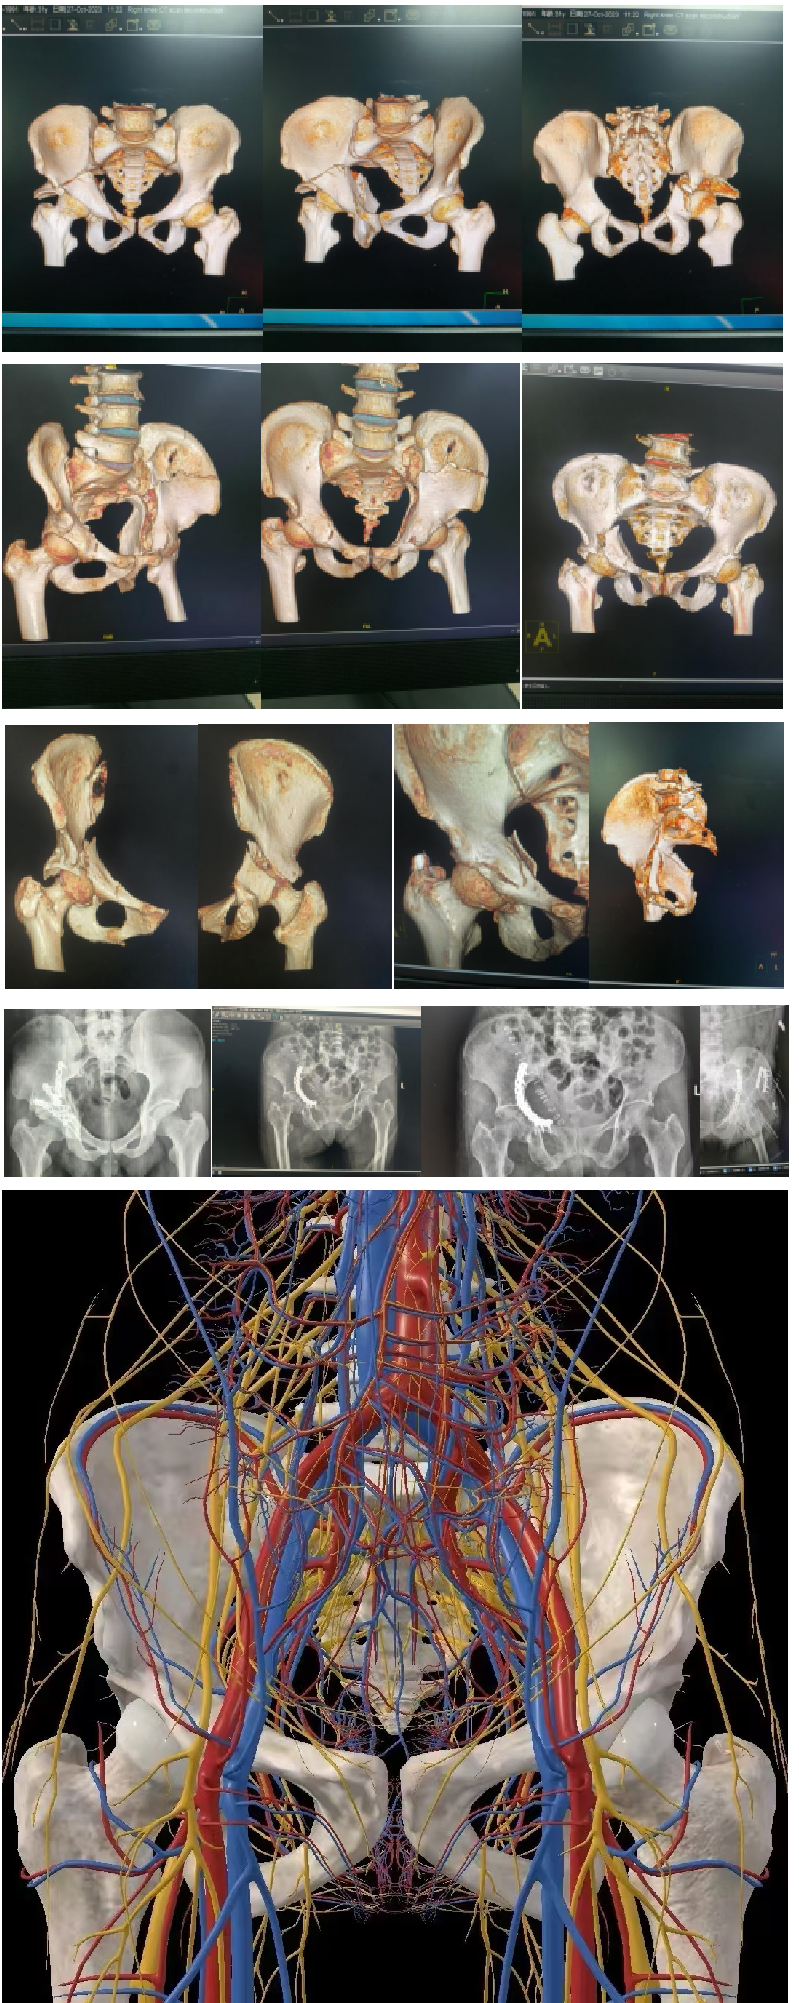

伤者入院后,医院立即组织重症监护室、胸外科、普外科及泌尿外科等多学科联合救治。骨关节外科医护团队进行认真细致的术前讨论,认真研究髂腹股沟入路、腹直肌外侧入路、后侧K-L入路,并根据患者的骨折类型,选择合适入路,制定周密的手术方案。骨盆髋臼骨折手术是创伤骨科手术的天花板,此区域存在髂外动静脉、股神经、死亡闭孔神经、精索(男)等组织,且骨盆髋臼立体结构复杂,复位及固定螺钉均存在较大难度。该手术虽是骨外科常规手术,但因伤者身体条件极为复杂,风险远超常规,最终在多学科团队(MDT)协作下顺利完成,患者现已康复出院。

术前及术后影像学资料